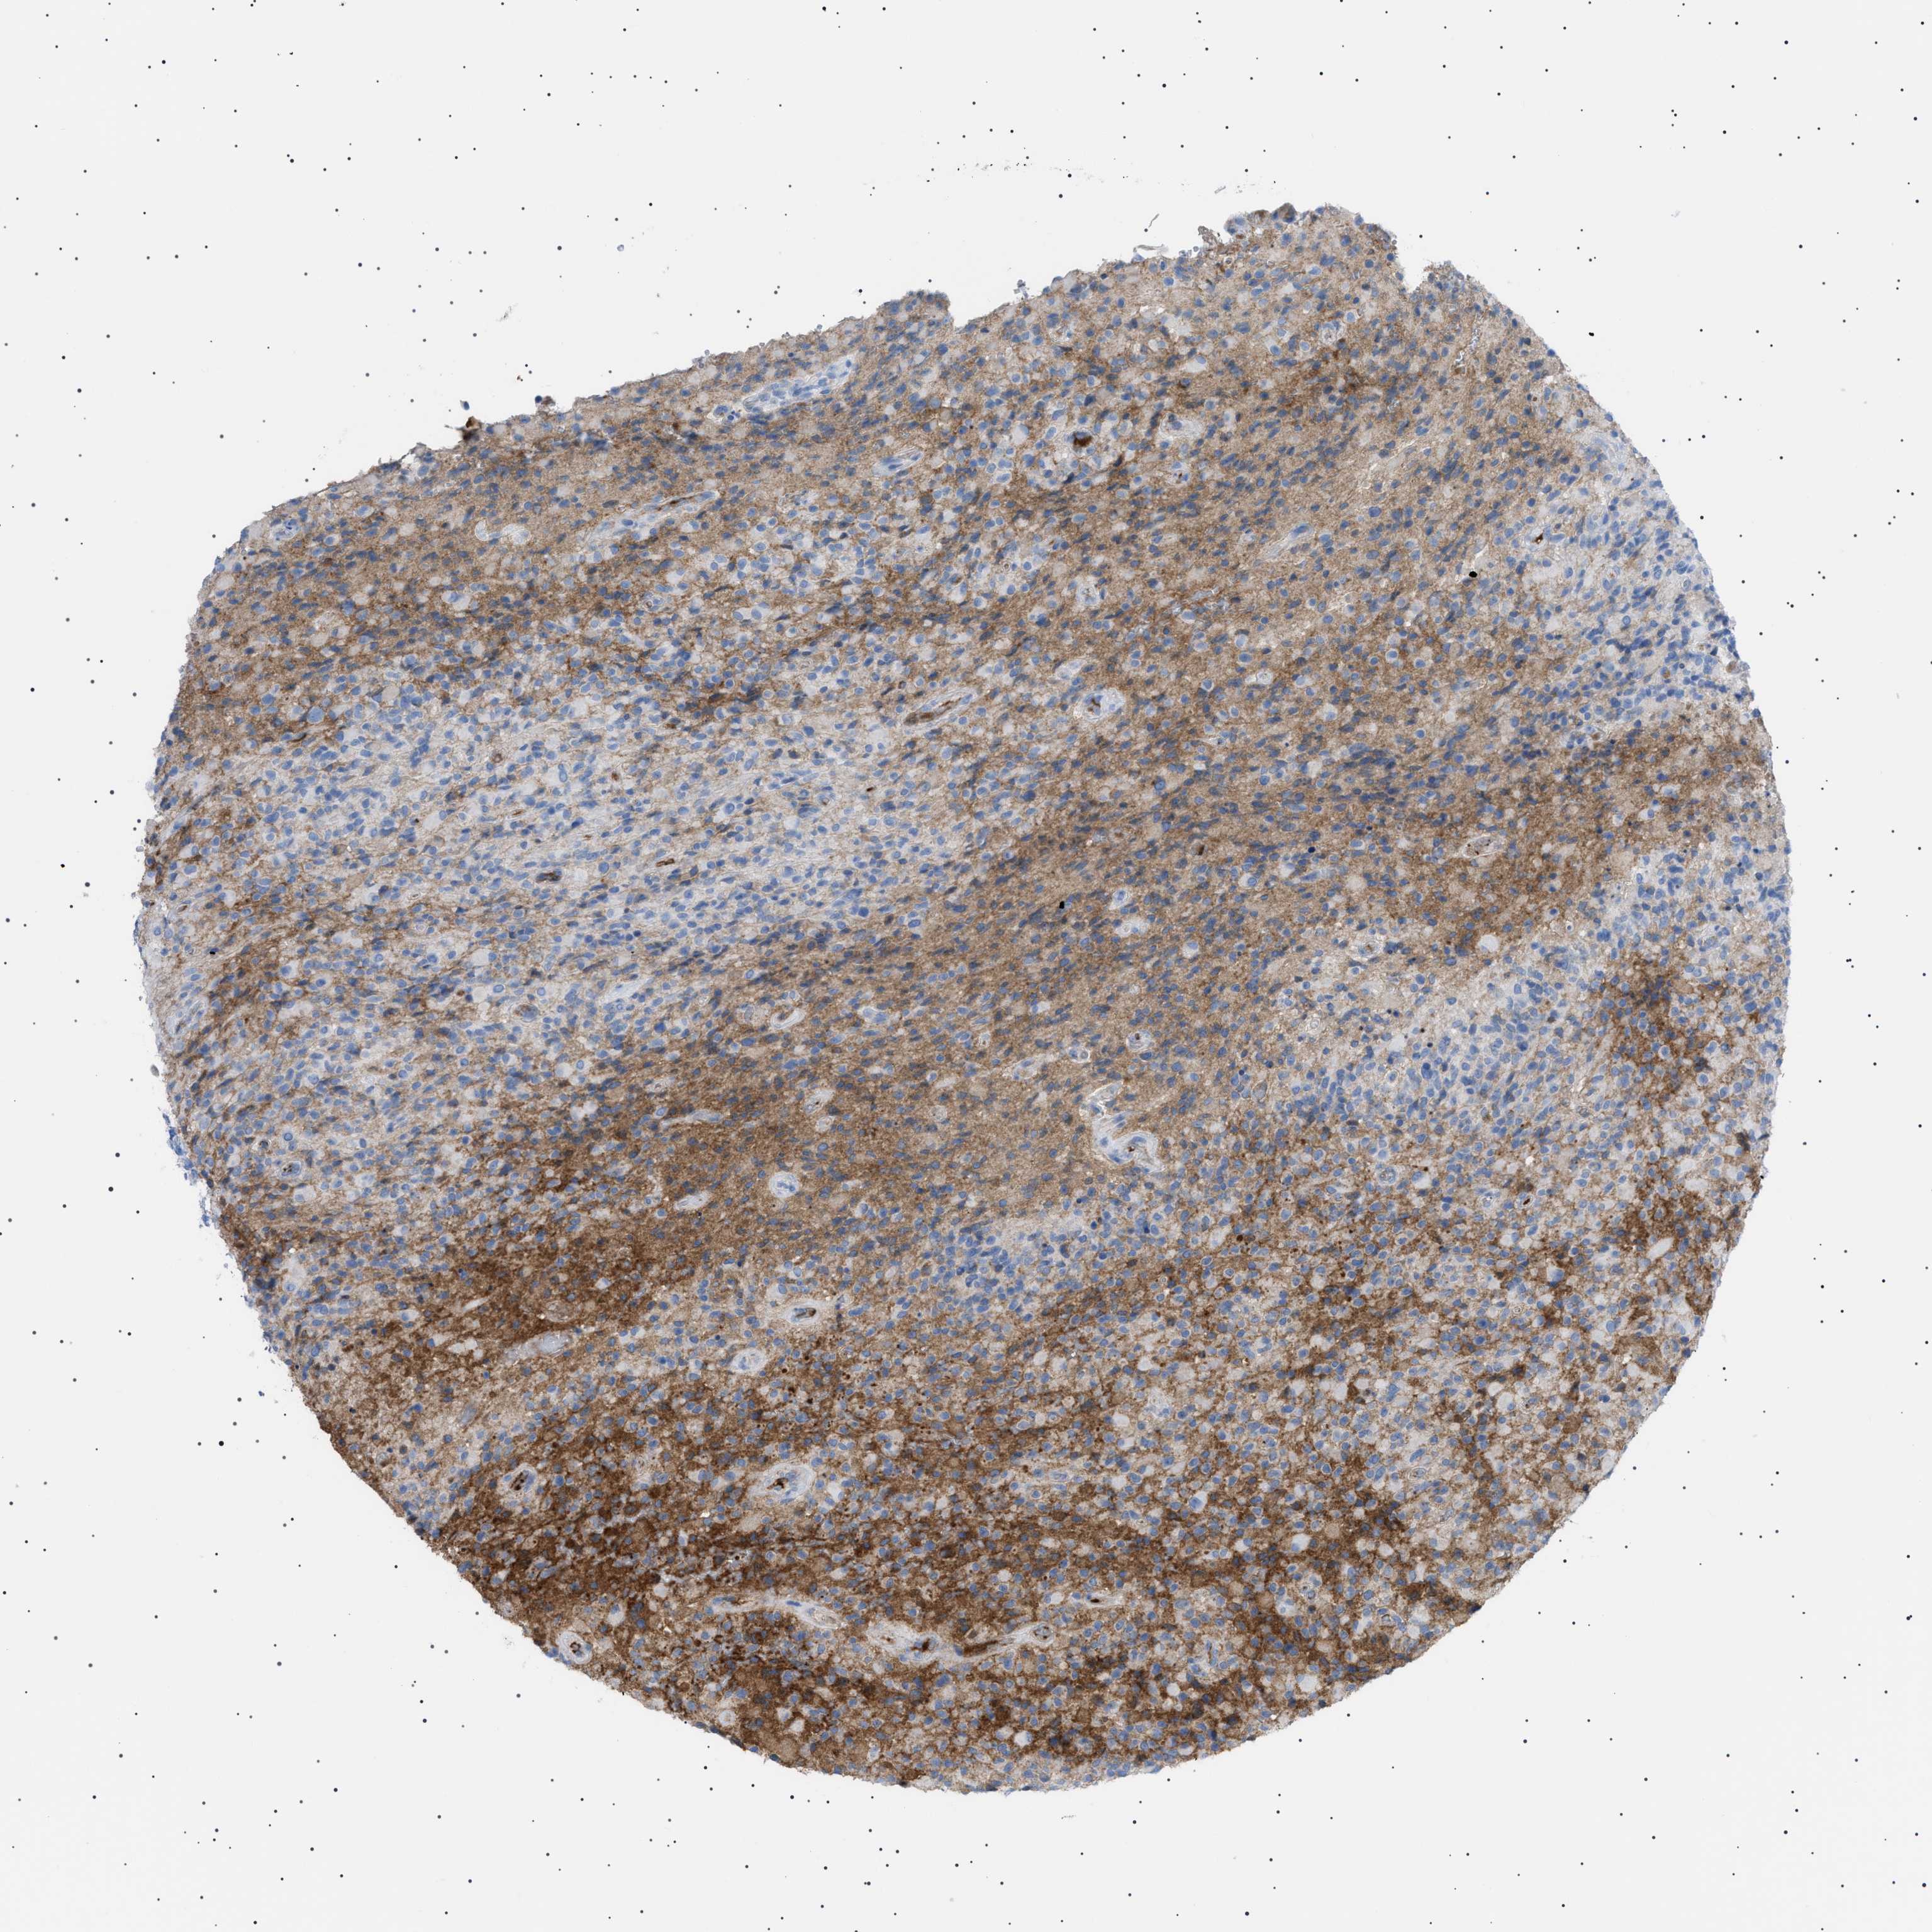

GLIOMA - Protein expressioni

A mouse-over function shows sample information and annotation data. Click on an image to view it in a full screen mode. Samples can be filtered based on level of antibody staining by selecting one or several of the following categories: high, medium, low and not detected. The assay and annotation is described here.

Note that samples used for immunohistochemistry by the Human Protein Atlas do not correspond to samples in the TCGA dataset.

Antibody stainingi

Antibody staining in the annotated cell types in the current human tissue is reported as not detected, low, medium, or high, based on conventional immunohistochemistry profiling in selected tissues. This score is based on the combination of the staining intensity and fraction of stained cells.

Each image is clickable and will lead to virtual microscopy that enables deeper exploration of all samples and also displays staining intensity scores, fraction scores and subcellular localization as well as patient and tissue information for each sample.

Antibody HPA060604

Antibody CAB016072

Glioma, malignant, Low grade

Glioma, malignant, High grade